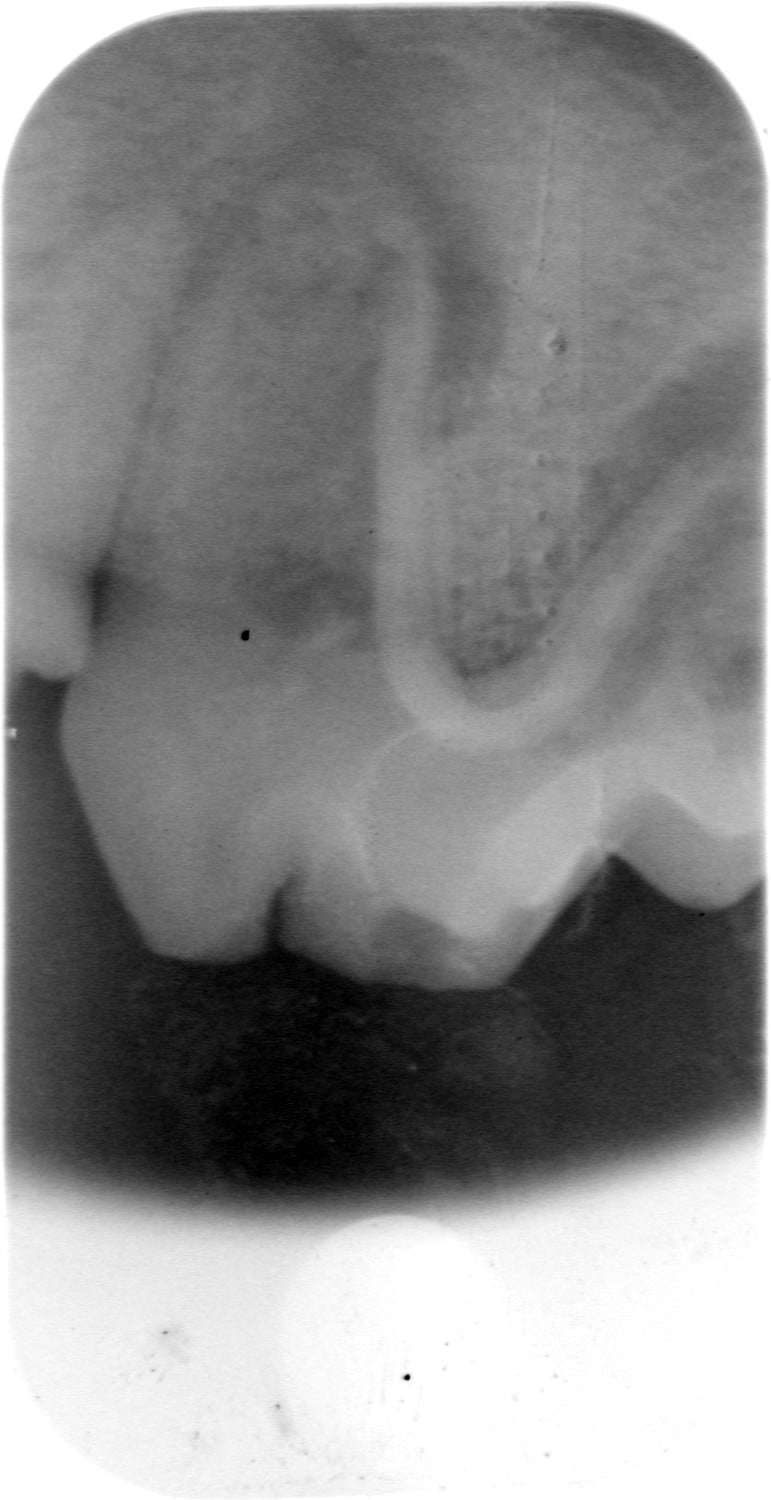

Röntgenbilder

(Fraktur + Wurzelentzündung durch Zahnstein)